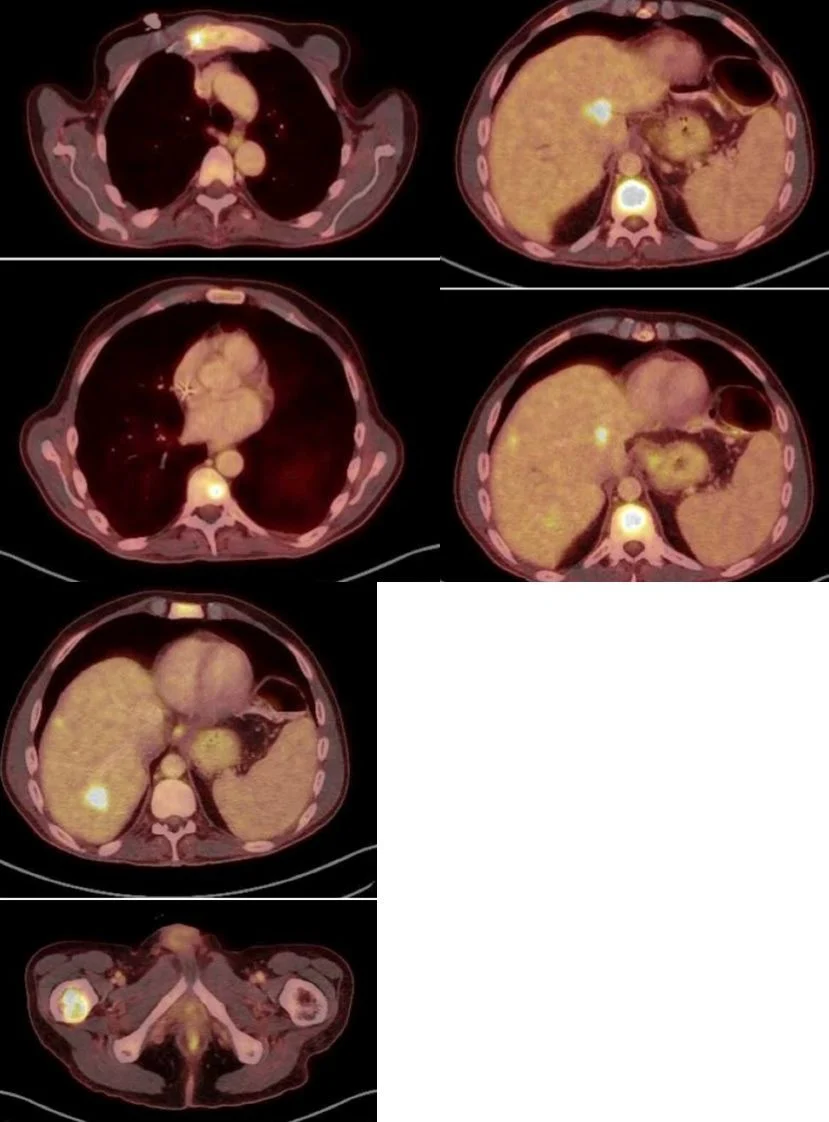

“Great discussions at today’s WIN Consortium in cancer personalized medicine international MTB of challenging cases including a case I presented of a patient with long-standing Crohn’s disease with metastatic jejunal adenocarcinoma with neuroendocrine features, MSS, EGFR and CDK6 amplification, among other alterations without available drugs, Ki67>90% with liver, bone, pleural and mesenteric metastases. Great discussion of diagnostic, disease monitoring and precision therapy options for the disease previously treated in the way CRC is treated but with prior progression with high proliferation index.

Future options for consideration included Lutathera pending a dotatate scan, palliative radiotherapy for symptomatic spine metastases, combinations that include double anti-EGFR blockade with Cetuximab plus erlotinib, targeting CDK6 with an anti-CDK4/6 inhibitor, TKIs including low dose regorafenib, anti-VEGF therapy, and targeting beta-catenin with mebendazol while still considering immunotherapy combinations with caveats due to EGFR amplification and Crohn’s disease in a later line of treatment.”